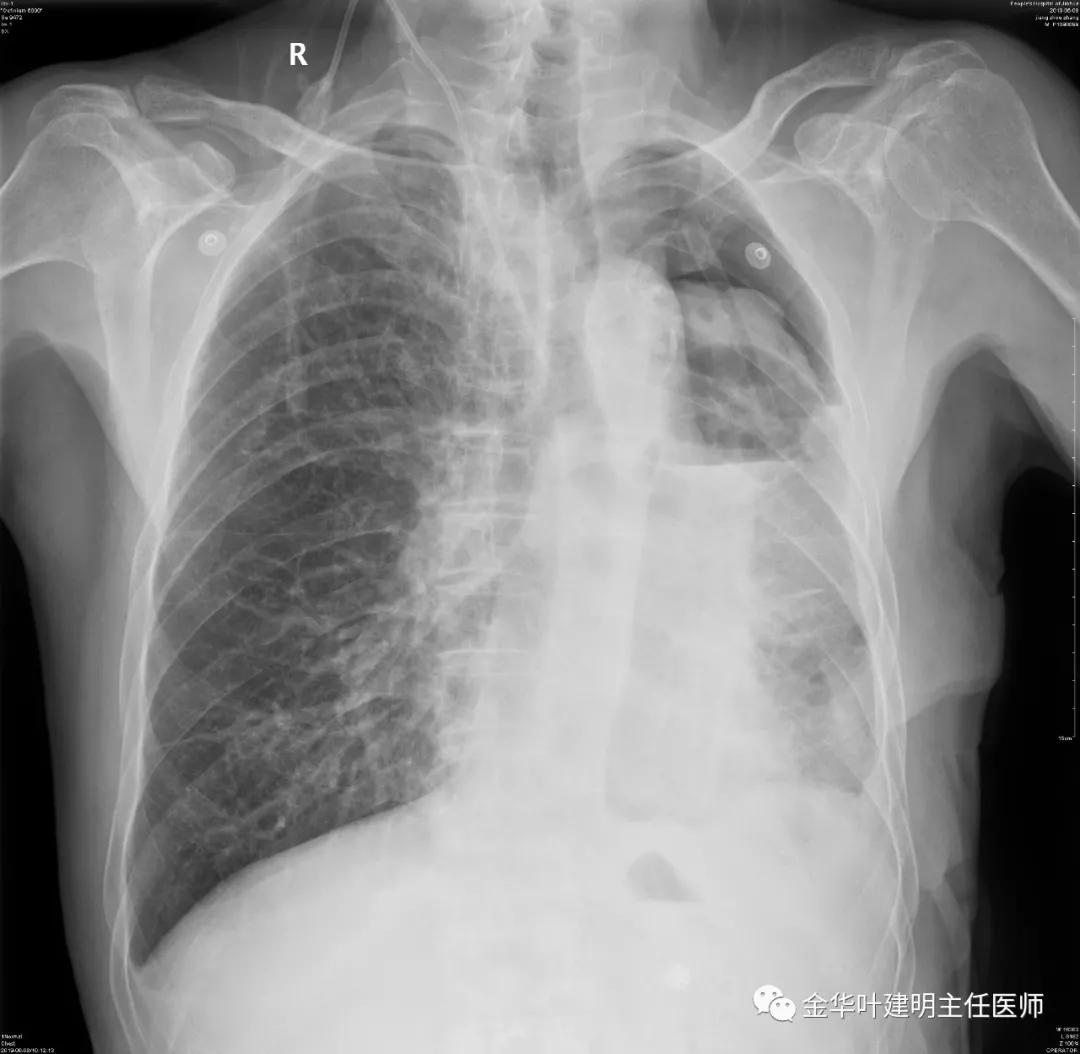

5.31下午7时,从早上开始算胸引700毫升,共900毫升;予以查床边,胸片,结果如下:

考虑左侧大量胸腔积液,遂进一步胸部CT检查: